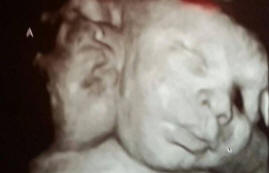

Asa i Ali Hamley rođeni su Robinim trideset četiri roditelja i Michelle. Na jeziku medicine, njihovo odstupanje naziva se dicefalnim parapagus, odnosno stanje blizanaca, kad su svi organi izvan isključujući ciljeve, imaju zajedničko.

Ovaj je slučaj zanimljiv jer obično takva djeca ne prežive. U jednom od hiljadu slučajeva žena može zatrudniti s takvim djetetom, već samo jedno dvoglavo dijete na milion obične djece uspeva da preživi.

Asa i Eli imaju tri pluća, i izuzev neozbiljnih poremećaji u srcu, njihovo je tijelo u savršenom redu.

Zbog činjenice da su gotovo svi organi i krvožilni sustav blizanci sami za dvoje, ne mogu se podijeliti, spasući život obojici.